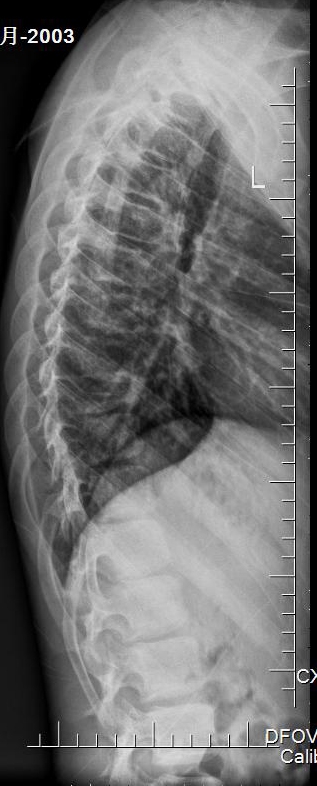

入院X片:胸9楔形改变,椎体高度损伤80%。

入院胸椎X片